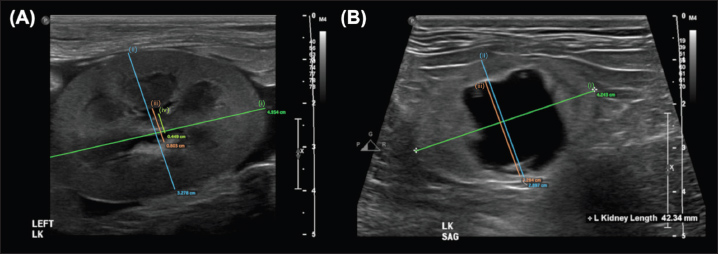

Discussion

Fig. 2. Examples of the DCU (A) and TCU (B) measurement methods, which had the highest interobserver agreement of all methods examined in this study.